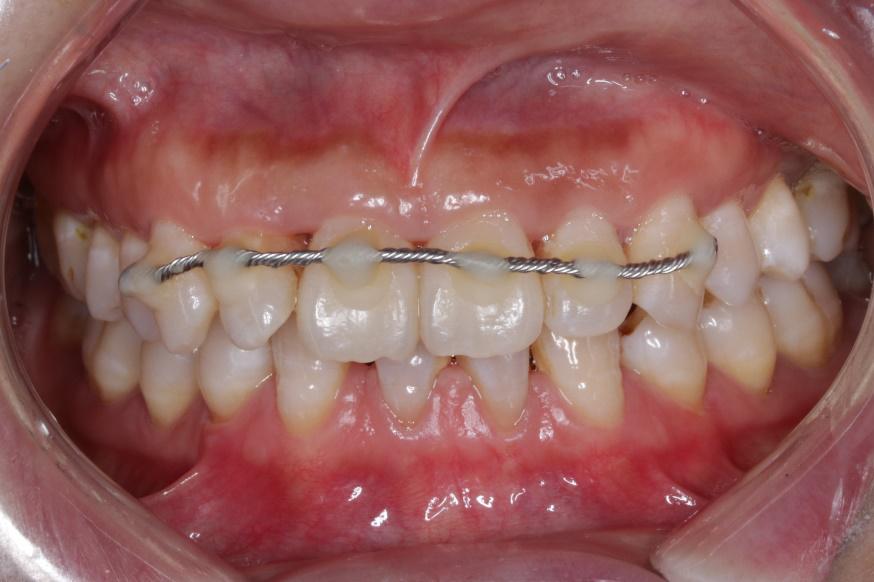

复位是在局部麻醉下进行的,医生试着将小明的门牙恢复到原来的位置,随后对外伤牙两侧的牙齿进行酸蚀,利用树脂以及钢丝对复位的门牙进行固定。在复位固定后,医生还对树脂和钢丝进行了调磨,让它们变的更光滑,尽量减少异物感以及对嘴唇的影响,同时对两颗门牙进行了调磨,减轻患牙的受力。

一阵忙碌后,小明的治疗暂时结束了,撞歪的门牙基本恢复了正常。

两周后医生为小明拆除了固位的钢丝,两颗门牙基本回到了原来的位置,检查确认门牙的牙髓活力尚存,暂时不需要治疗。

复位的两颗门牙